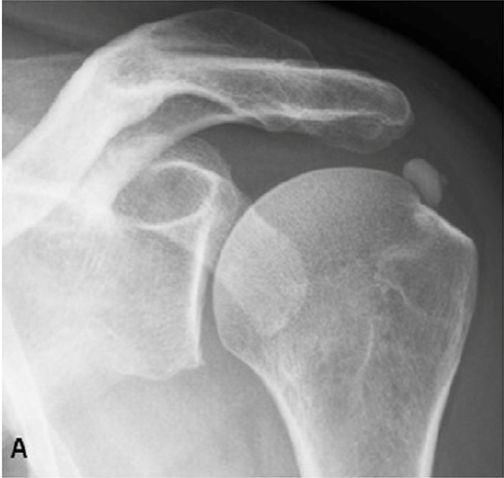

Ακτινολογική ταξινόμηση της ασβεστοποίησης στον ώμο (Gartner and Hayer)

Ανάλογα με την απεικόνιση στην ακτινογραφία ταξινομείτε ως εξής:

| Τύπος Ι : Ομαλά όρια, αυξημένη πυκνότητα ασβέστωσης. Φάση σχηματισμού | Τύπος ΙΙ: Σχήμα ομαλό, πυκνό ή οξύ, περιοχές ακτινοδιαπερατές. Φάση σταθεροποποίησης | Τύπος ΙΙΙ: Διάφανη, νεφελώδης εμφάνιση, χωρίς σαφή όρια. Φάση απορρόφησης |